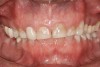

Figure 4   Indentations on tongue caused by forceful pressing of tongue on lingual surfaces. By pushing the tongue anteriorly, the airway is opened.

Figure 4

Bruxism and airway appear to be related to the patient’s attempt to develop a patent airway during a desaturation episode. The majority of SB episodes occurs in a supine position and may be associated with either a reduction in the airway passage or increase in its resistance. During resumption of ventilation following apnea, a co-activation of both jaw-opening and jaw-closing muscles produce dilation of the upper airway. This permits a rise in inspiratory flow and reduces upper airway resistance.37 It has been reported that 99% of all rhythmic masticatory muscle activities were associated with a change in the respiratory amplitude and frequency.19 Changes in lateral tongue contours, long associated with nocturnal bruxers, can now be explained. The patient attempts to provide a patent airway by activating the tongue muscles and forcing the tongue off the airway and against the teeth (Figure 4).